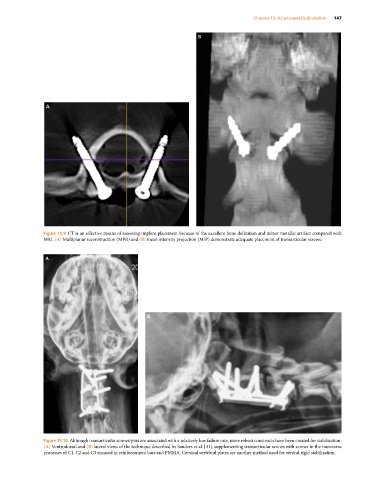

Figure 15.9 CT is an effective means of assessing implant placement because of the excellent bone definition and minor metallic artifact compared with

MRI. (A) Multiplanar reconstruction (MPR) and (B) mean intensity projection (MIP) demonstrate adequate placement of transarticular screws.

Figure 15.10 Although transarticular screws/pins are associated with a relatively low failure rate, more robust constructs have been created for stabilization.

(A) Ventrodorsal and (B) lateral views of the technique described by Sanders et al. [31], supplementing transarticular screws with screws in the transverse

processes of C1, C2 and C3 encased in reinforcement bars and PMMA. Cervical vertebral plates are another method used for ventral rigid stabilization.